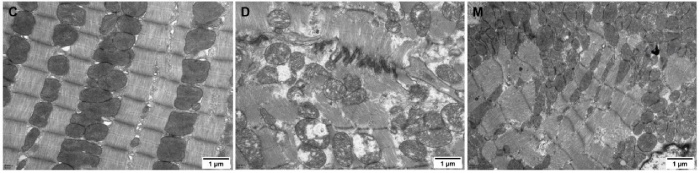

該研究利用透射電鏡測定了MOTS-c對糖尿病心肌超微結構的影響。糖尿病引起心肌纖維排列紊亂和線粒體結構的異常改變,包括心肌細胞排列不規則、嵴破裂、腫脹和空泡化(圖2)。MOTS-c治療糖尿病大鼠顯著降低心肌線粒體損傷,改善心肌纖維和線粒體結構(圖2)。研究還通過測定檸檬酸合酶的活性,測定了線粒體功能。D組大鼠檸檬酸合酶的活性顯著降低,C組和M組的檸檬酸合酶的活性無統計學差異(圖3g)。

圖2. 各組大鼠心肌組織透射電鏡圖像